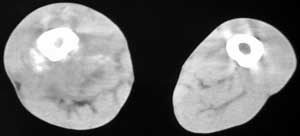

男56涨疼5-6月

右股骨下端包绕股骨见巨大软组织肿块,密度部俊,周围见瘤骨,下端骨皮质侵蚀变薄,骨质周围无骨膜反应, 考虑右股骨软骨肉瘤。

右股骨下段周围软组织肿块伴钙化,相邻股骨骨皮质受累,考虑软组织来源恶性病变

右股骨下段骨肉瘤,软组织内瘤骨,软组织肿块。